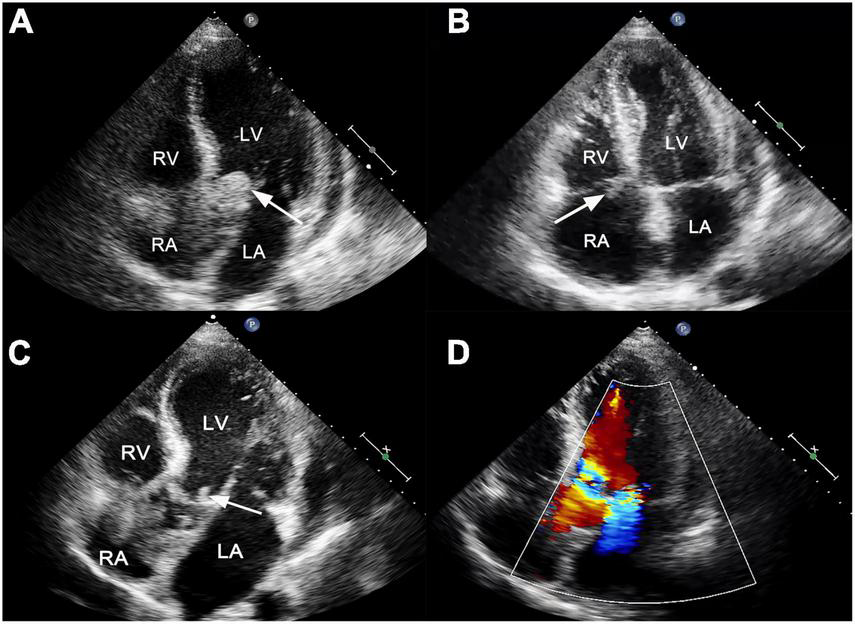

He presented to the emergency department with persistent fever (38°C) and fatigue 1 month after surgery. The blood pressure was 109/71 mmHg, breathing rate was 16 breaths/min, pulse was 88 beats/min, and temperature was 36.5°C. Laboratory results showed white blood cell 19.6 × 109/L, hemoglobin 95 g/L, platelet count 106 × 109/L, C-reactive protein 195 mg/L, B-type natriuretic peptide 761.8 pg/ml, hypersensitivity troponin T 0.174 ng/ml. Electrocardiographic analysis revealed a first-degree atrioventricular block. A heart examination showed a murmur at the aortic area. Transthoracic echocardiogram (TTE) revealed a large (25 mm × 22 mm), iso-echogenic, irregular vegetation on the ventricular side of the prosthetic aortic valve (Figure 1A) winging back and forth during the cardiac cycle. In addition, a large (16 mm × 9 mm) tricuspid valve vegetation with obvious mobility was also presented (Figure 1B). IE was suspected according to the modified Duke criterion (4). Therefore, vancomycin (1,000 mg, every 12 h) and gentamicin (240 mg, every 8 h) were given for infection control. Rifampin was orally taken (0.3 g, every 8 h). In addition, enoxaparin sodium injection (0.8 ml, every 12 h) and warfarin (5 mg a day) were administered to prevent further vegetation generation. The diagnosis of Staphylococcus epidermidis endocarditis was confirmed by blood culture on day 4 after admission. Differential diagnoses included intracardiac thrombus, cardiac myxoma, non-bacterial thrombotic endocarditis and valve calcification.

FIGURE 1

(A) Transthoracic echocardiogram showed a large, mobile vegetation on the ventricular side of the prosthetic valve (white arrow). (B) A vegetation was also visible on the tricuspid valve (white arrow). (C) Transthoracic echocardiogram reexamination showed residual vegetations on prosthetic aortic valves with reduced size (white arrow). (D) The new mitral valve moderate regurgitation. LA, left atrium; LV, left ventricle; RA, right atrium; RV, right ventricle.

On day 28, the patient presented with sudden convulsion. Enhanced CT scanning revealed left occipital cerebral embolism (Figure 2E). Deproteinized calf serum injection (0.8 g once a day) was given to improve brain blood circulation. He underwent a TTE reexamination on day 31, showing that aortic valve and tricuspid valve vegetations were still present while the aortic valve vegetation was smaller compared with the last time (Figure 1C). However, a new mitral valve regurgitation has emerged (Figure 1D). Unfortunately, he presented with decreased muscle tone in the right limb on day 35, and the subsequent CT scan showed another new spot of cerebral embolism.